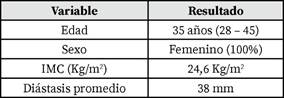

Características Demográficas y Preoperatorias (Tabla 1)

La edad promedio fue de 35 años (28 - 45). La edad promedio reportada en otras series de REPA o técnicas similares tiene un rango similar, por ejemplo, 37 años, Bayoux 2023(2), media 38 años (rango 24-66), Juárez Muas 2019(3), media 36.6 años (rango 1877), Kiudelis 2024(16).

El Índice de Masa Corporal (IMC) promedio fue de 24.6 kg/m2. Este valor se encuentra dentro del rango de peso normal. El IMC promedio en otras series publicadas también varía, por ejemplo, 32 kg/m2, Bayoux et al(2), 27.4 kg/m2 (rango 22-35), Bellido Luque 2015(7), media 29.0 kg/m2 (rango 3.6), Dong 2021(13), media 28.3 kg/ m2 (rango 25.1-33), Gandhi 2024(9), media 28.9 kg/m2, Shinde 2022(15), media 24.28 kg/m2 (rango 21.6-34.8), Mehta 2024(14).

Todas las pacientes presentaban diástasis de los músculos rectos abdominales (DRA). Definida comúnmente como una separación de los músculos rectos mayor a 2.2 cm o 22 mm(12). La diástasis promedio reportada a nivel supraumbilical fue de 38 mm (32 - 42). Otras fuentes reportan medidas promedio como: 39.3 mm 3 cm por encima del ombligo, Bellido Luque 2015(7), media 3.33 cm, Brucchi 2025(17), media 3.5 cm (rango 2.6-5 cm), Mehta 2024(14), media 5.22 cm (rango 2.5-15), Cuccomarino 2022(11).